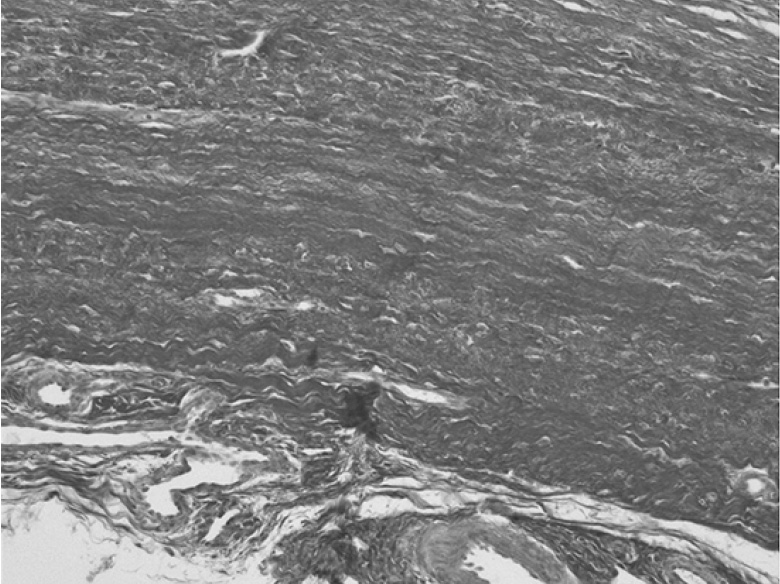

Рис. 2. Срез стенки кисты Бейкера (пикрофуксином по Ван Гизону, ×100). Видно обилие параллельно ориентированных коллагеновых волокон.

Fig. 2. A section of the wall of the Baker’s cyst (picrofuchsin according to Van Gieson, ×100). An abundance of parallel-oriented collagen fibers is shown.

Клеточный состав стенки кисты был представлен фиброцитами, макрофагами, однокапельными адипоцитами и лимфоцитами. В обоих слоях выявлены единичные кровеносные сосуды (в основном капилляры). Электронограммы демонстрировали исчерченные коллагеновые волокна в обоих слоях стенки кисты. Клетки фиброцитов/фибробластов располагались между многочисленными жировыми клетками, имели слаборазвитые органеллы, многочисленные отростки (рис. 3).